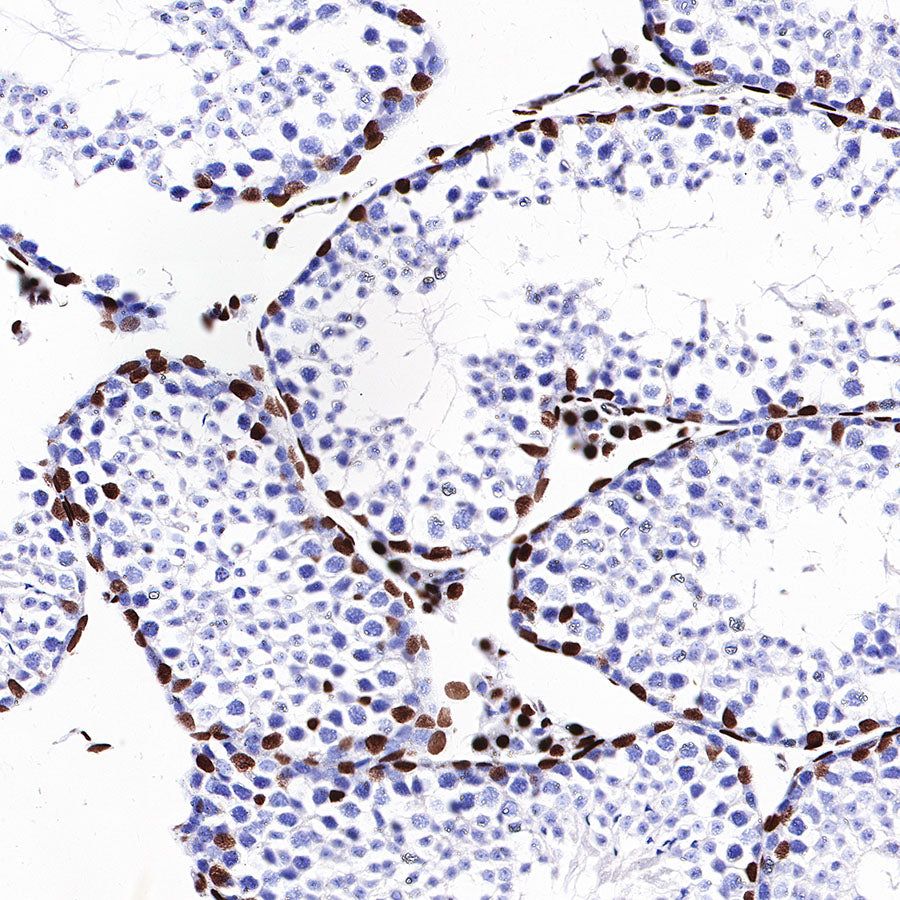

Immunohistochemistry